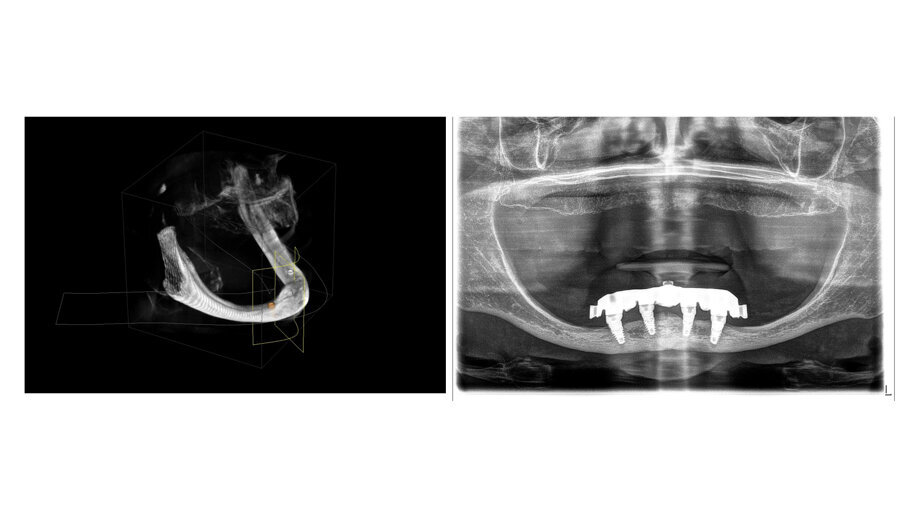

In this case, a patient presented with extremely atrophic bone in the mandible, with four short implants placed between the dental nerve foramen (Figs, 10a, 10b). After some time, patients wearing this kind of restoration with prefabricated teeth, their muscle activity increase considerably, which very often leads to fracture or debonding of the prefabricated teeth (Fig. 12). A combination of a rigid metal structure over the telescopic bar and a thimble structure made of PEEK (Fig. 13, 14) works as base for the final restorations. These were milled out of a BRILLIANT Crios disc either as single tooth units or bridges and cemented on the thimble structure (Figs. 15-17). Using BRILLIANT Crios instead of prefabricated teeth, we can increase the strength of the restoration, have good aesthetics and keep the weight low for this kind of prosthesis.

Figs. 10a and 10b : Patient with extremely atrophic bone in the mandible with four short implants placed between the dental nerve foramen